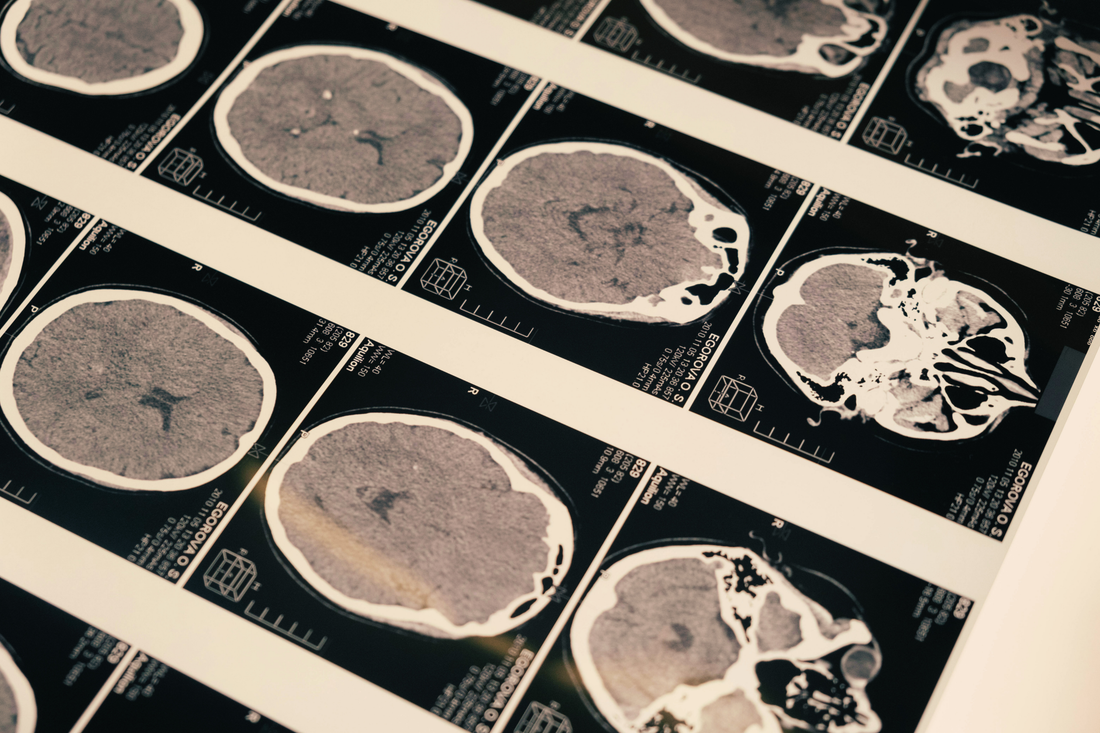

Realidad: La neurociencia moderna, a través de técnicas avanzadas como la resonancia magnética funcional (fMRI), ha demostrado que utilizamos virtualmente todas las áreas de nuestro cerebro. Incluso cuando estamos en reposo, nuestro cerebro está increíblemente activo, orquestando funciones vitales y preparándose para el siguiente desafío. Cada región cerebral tiene un propósito específico y trabajan en conjunto, como una sinfonía perfecta. Un artículo de revisión en Cerebrum: The Dana Forum on Brain Science, escrito por Samuel E. Gandy y Barry Gordon, desmiente este mito al explicar cómo las técnicas de imagen cerebral y la evidencia de daño cerebral demuestran que el cerebro está activo en su totalidad. Si solo usáramos el 10%, un daño en el 90% restante sería imperceptible, ¡y sabemos que cada pequeña lesión cerebral puede tener un gran impacto!